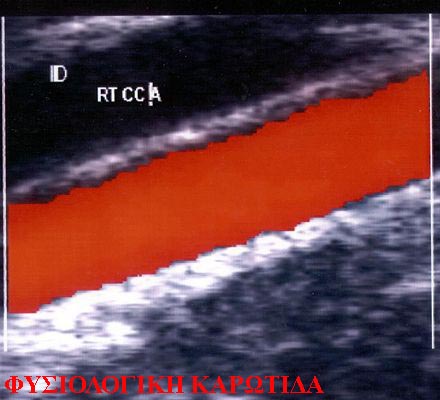

TRIPLEX ΓΓΓΓΓΓΓΓΓ ΓΓΓ ΓΓΓΓΓΓΓΓΓΓΓ ΓΓΓΓΓΓΓΓ

Γ ΓΓ ΓΓΓΓ ΓΓΓΓΓΓΓΓΓ ΓΓΓΓΓΓΓ, ΓΓΓΓΓΓΓΓΓ ΓΓΓ ΓΓΓΓΓΓΓΓΓ ΓΓΓ ΓΓΓΓΓΓΓΓΓΓΓ ΓΓΓΓΓΓΓΓ ΓΓ ΓΓΓ ΓΓΓΓΓΓ